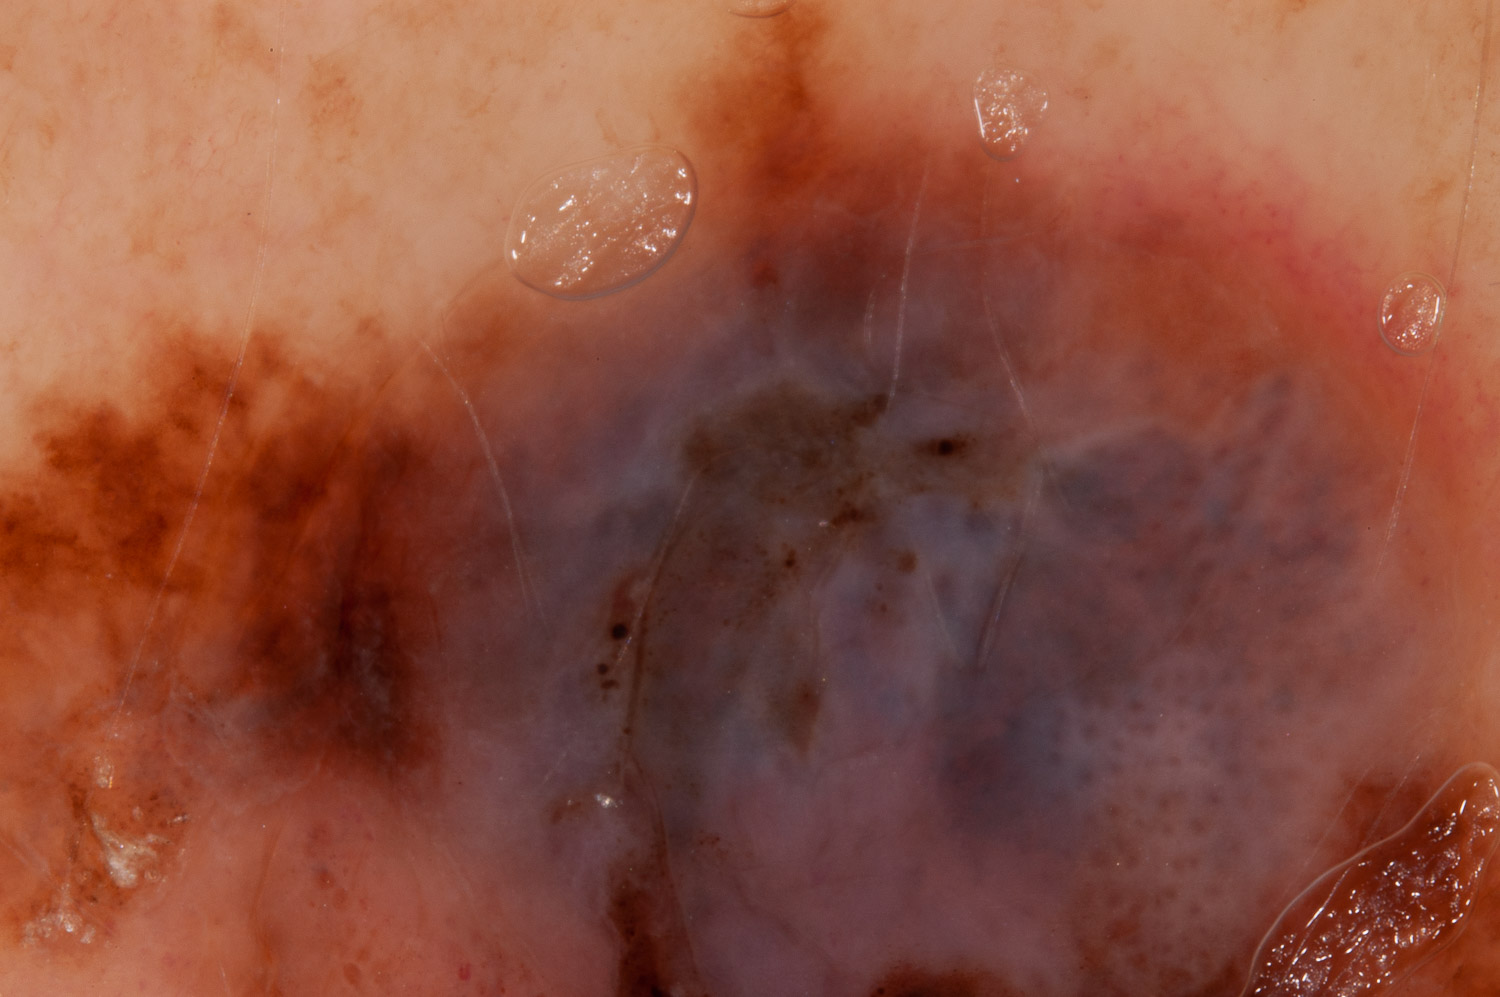

Case: 218